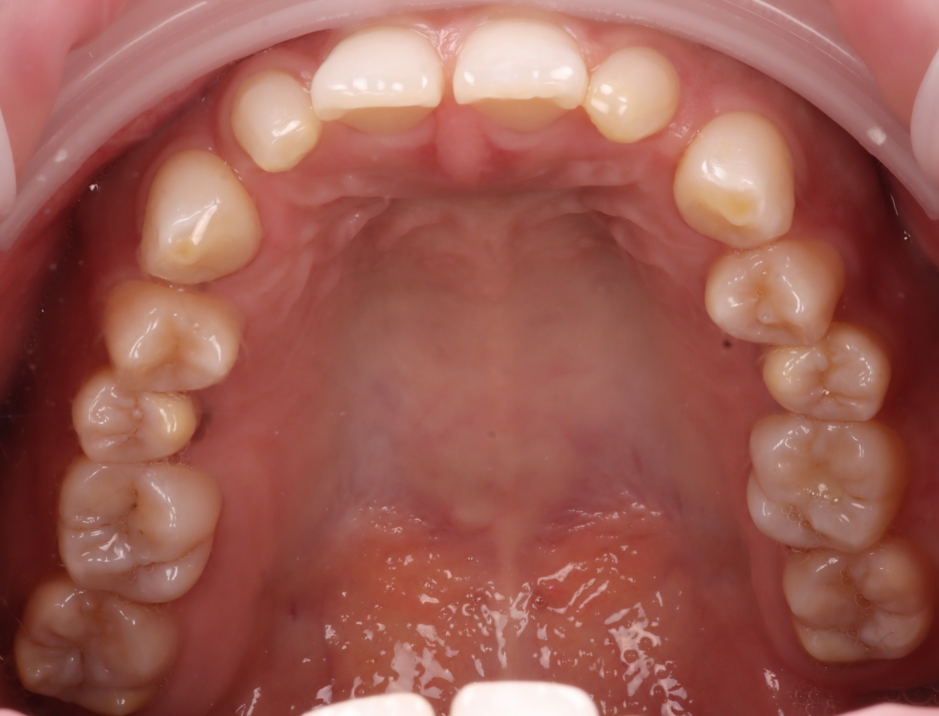

또, 윗니와 아랫니가 워낙 깊게 물리고 있었습니다.

그래서 치아를 좌, 우로 움직일 때 아랫니와의 간섭이 많이 되어 아래 앞니를 조금 다듬어야 할 수도 있음을 설명드렸습니다.

아래 앞니가 고르지 않고, 조금씩 틀어진 부분이 있어 그 부분이 걸릴 수 있겠더라고요.

그래서 이 부분은 레진이 완료된 후 확인해 보기로 했습니다.

촬영일 : 251203